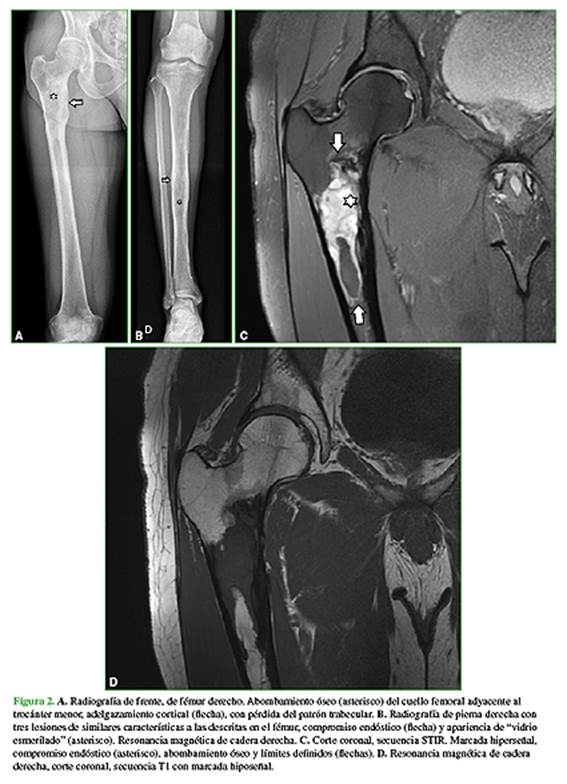

En febrero de 2020, consulta a un traumatólogo de nuestro centro. En el examen físico, la movilidad de la cadera y la rodilla es completa, sin dolor en el miembro inferior derecho. Además, se palpa una tumoración en la zona anteroexterna proximal de la pierna derecha de aproximadamente 8 cm, profunda, elástica, no dolorosa (Figura 1) que, según el paciente, tenía desde los 17 años de edad y su crecimiento era lento. Se solicitan nuevas radiografías y una resonancia magnética de cadera y pierna, y una ecografía de la masa de partes blandas en la pierna (Figura 2).

En las radiografías, se visualiza como lesiones intramedulares diafisarias, radiolúcidas, con apariencia de “vidrio esmerilado” y pérdida del patrón trabecular normal, compromiso endóstico y adelgazamiento de la cortical con áreas respetadas. Los márgenes son definidos. No se observa una reacción perióstica. Las imágenes de la tomografía computarizada confirman la presencia de lesiones homogéneas con apariencia de “vidrio esmerilado”. Puede haber áreas quísticas y calcificaciones. En la resonancia magnética, se observan lesiones con baja señal en las secuencias T1 y alta señal en las secuencias T2. Puede haber un halo hipointenso a su alrededor en las secuencias T1 y T2. Como es una lesión benigna, tiene difusión facilitada con valores de coeficiente de difusión aparente por encima de 1,1 x 10-3 mm2/s.1,2,10